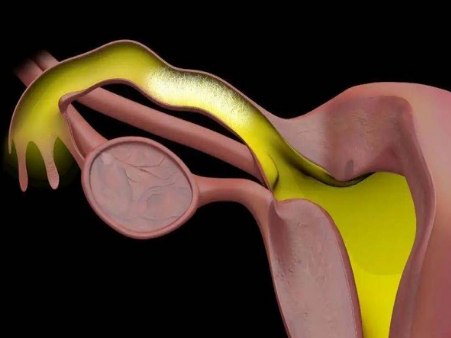

引起女性不孕的原因有很多一部分来自于输卵管疾病,比如因为感染引起的,还有患有子宫内膜异位症,又或者是做完了盆腔手术创伤等引发的,而想要检查输卵管堵塞的情况比较好的方式就是做造影检查,以此来判断阻塞部位,结合具体的堵塞情况给予一定的治疗,因此输卵管造影在临床上也被广泛使用,可能有些朋友会对输卵管造影的过程感兴趣,所以下面就给大家详细图解一下。一般输卵管应呈水平走行或稍向下行至壶腹部时又稍向上行或在子